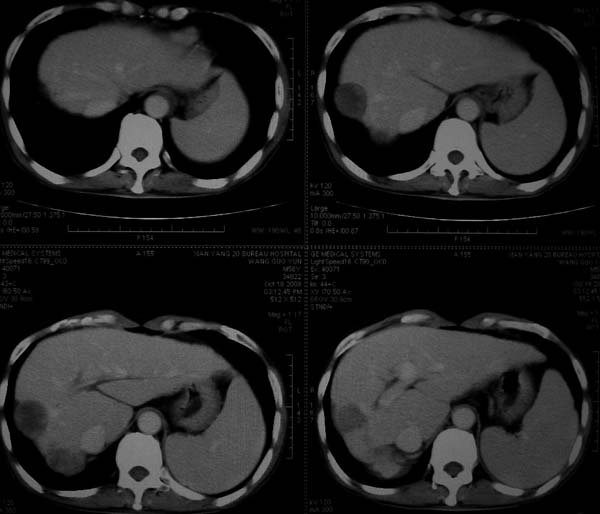

标题: CT16292:男,53岁,上腹部不适2月,B超发现肝内占位病变。 [打印本页]

标题: CT16292:男,53岁,上腹部不适2月,B超发现肝内占位病变。

符合肝ca增强,\"快进快出\";肝叶比例失常,右叶萎缩,肝裂增宽,脾大,肝硬化可能.

肝脏体积变小,肝裂增宽,分布异常,肝尾叶增大,脾肿大,考虑肝硬化可能性大,右肝病灶呈现早期充盈,延迟强化考虑肝内胆管细胞癌可能,不除外血管瘤

肝叶比例失调,左叶增大,肝裂增宽,脾脏增大,门脉增宽,肝右叶包膜下多发结节样阴影,增强虽说强化幅度不大,但还是符合快进快出特点;考虑肝硬化、脾大、结节型肝癌。胆管细胞癌多有延时强化、肝包膜凹陷征、周围胆管扩张等特点,本例明显不符;故不考虑。